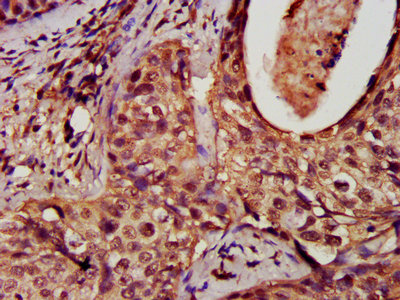

Immunohistochemistry analysis of human cervical cancer using CSB-PA007078EA01HU at dilution of 1:100